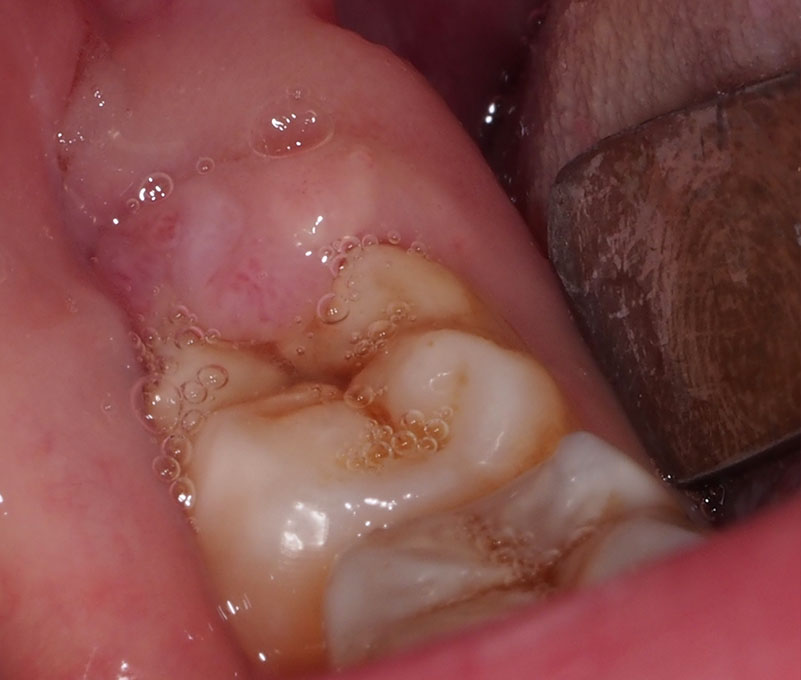

The above photo shows the healed site after the procedure. EE has not had another bout of pain and swelling since the procedure was done.